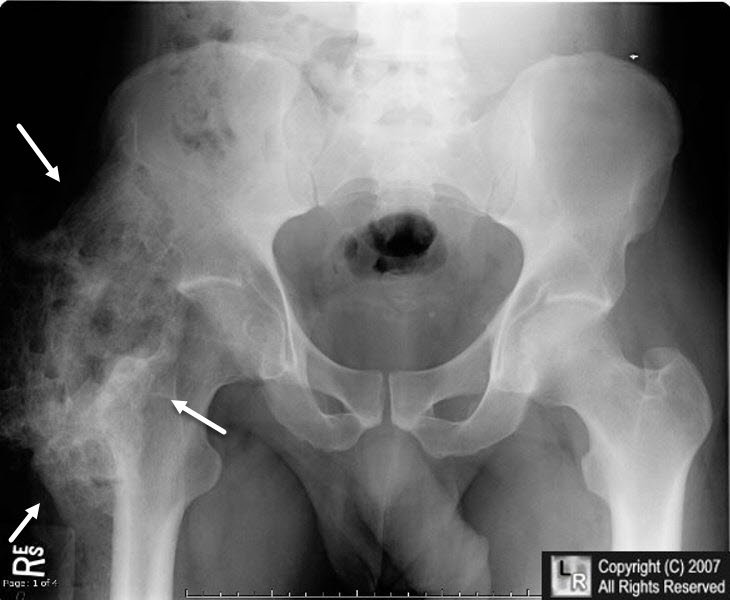

(Heterotopic ossification)

هذه الحالة قد تحدث بعد إصابات الجهاز العصبي المركزي (المخ أو الحبل الشوكي) او بعد جراحة مفصل الفخذ الصناعي حيث يحدث تكون للعظام فى الأنسجة الرخوة المحيطة بمفصل الفخذ مثل العضلات والأوتار والأربطة و قد تزداد هذه العظام صلابة بالوقت فى بعض الحالات حتى تصبح قوية مثل العظام الطبيعية بعد 6 – 18 شهرا مما يؤدي الى تيبس كامل بالمفصل و حدوث تورم حوله.

و يمكن تشخيص هذه الحالة مبكرا بإستخدام تحليل معين أو عمل مسح ذري للعظام و لكن نادرا ما يتم إجراء ذلك. أما فى الحالات المتأخرة فيكفي عمل أشعة عادية لتشخيص الحالة, حيث تظهر الأشعات العظام الجديدة حول المفصل.